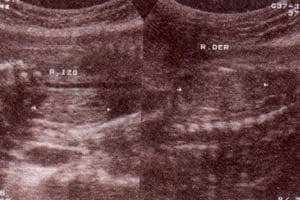

fig. 82.– (a,b). ectasia piélica izquierda grado i y grado ii. 26 semanas. corte transversal y longitudinal del riñon izquierdo. |

| fig. 82. – (d). 34 semanas. corte transversal ectasia piélica | fig. 82.– (e). 35 semanas. corte longitudinal y transversal ectasia pielocalicial. |